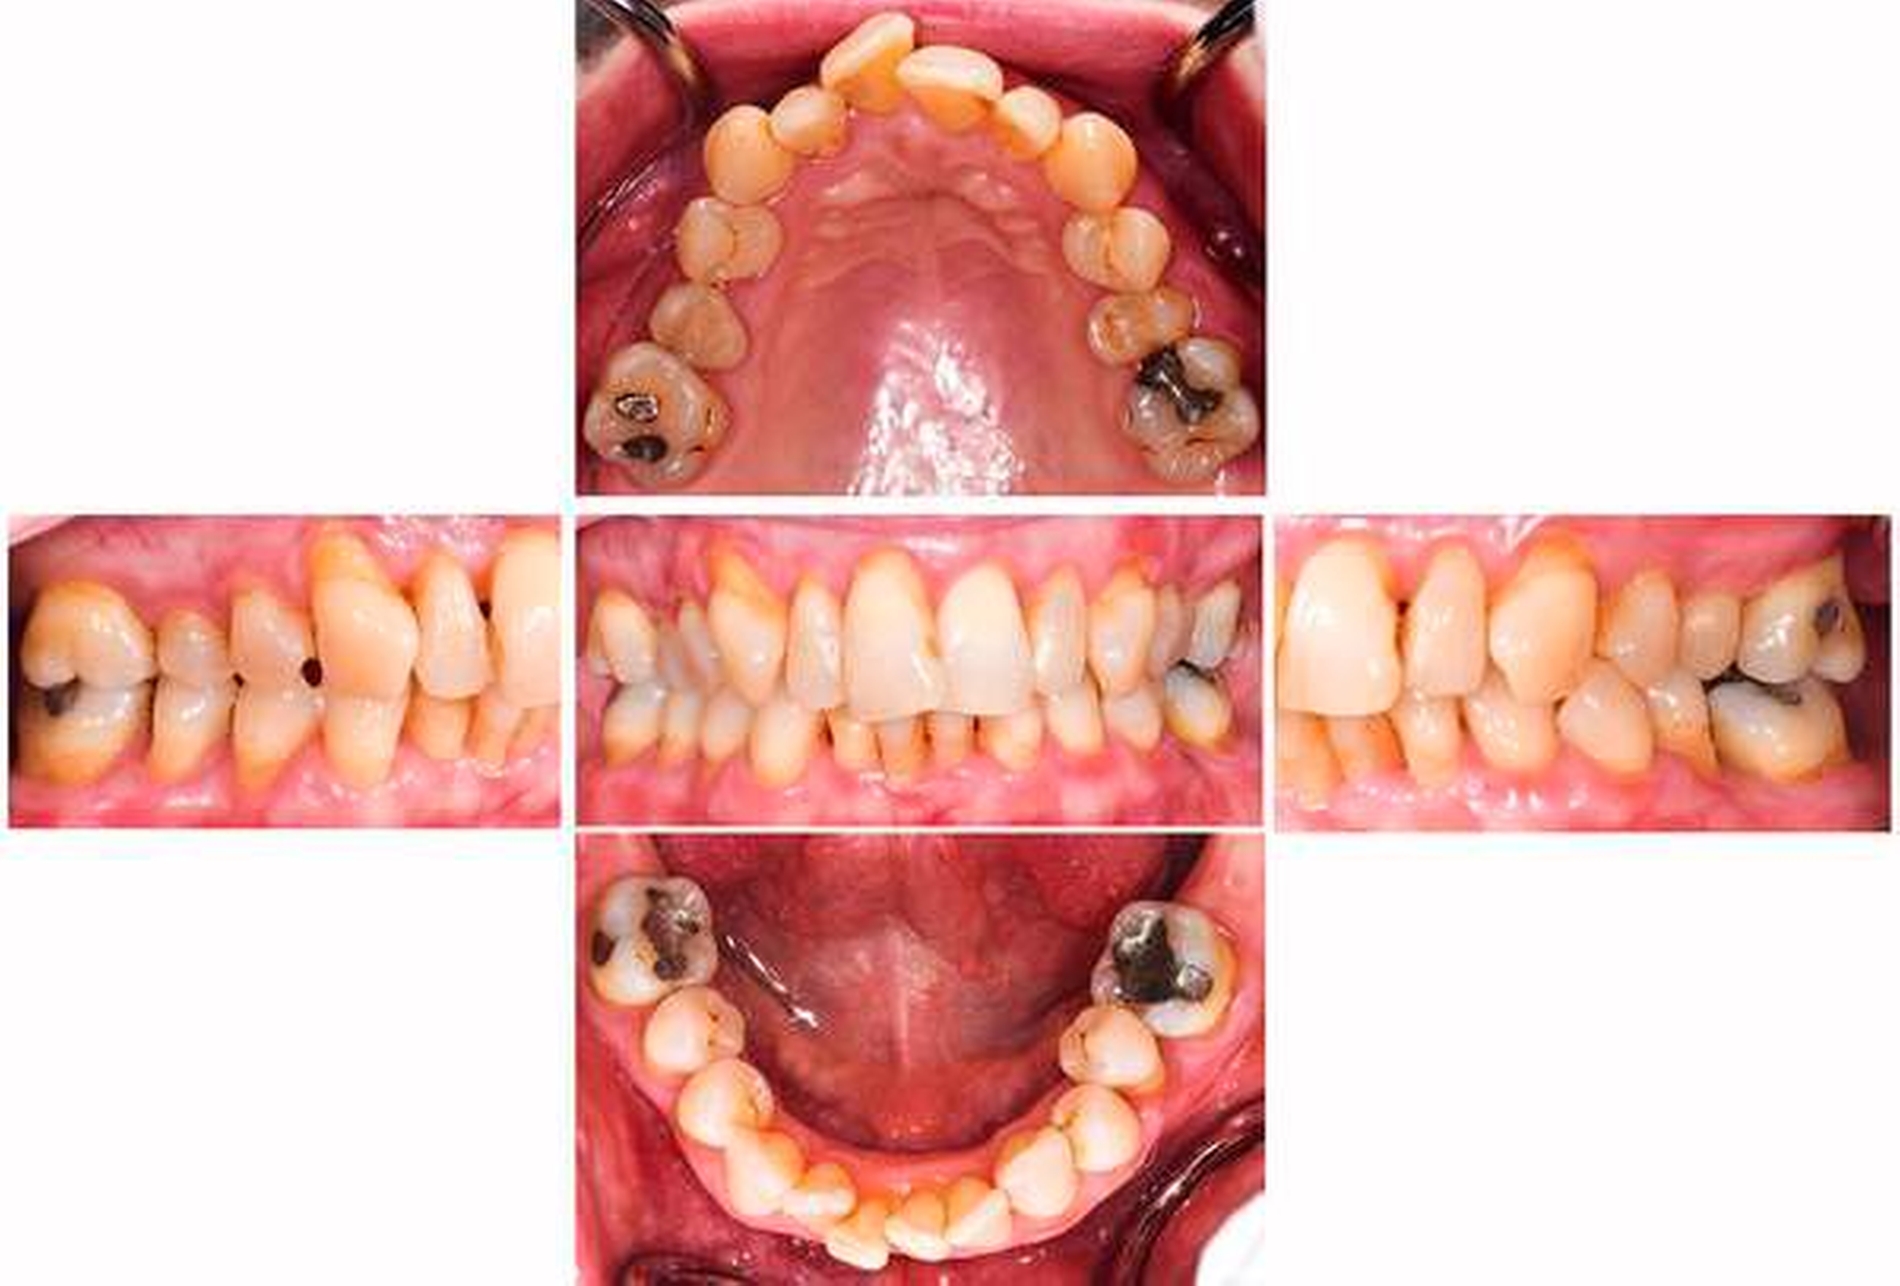

Es lagen Gelenkgeräusche und eine Deviation bei Mundöffnung bei ansonsten unauffälligem extraoralem Befund vor. Die Schleimhäute waren ohne pathologischen Befund. Es fehlten die Zähne 17, 27, 37, 47. Das Gebiss war konservierend versorgt, am Zahn 21 zeigte sich eine erneuerungsbedürftige Füllung (Sekundärkaries). Alle Zähne reagierten auf den CO2-Kältetest, Zahn 26 zeigte eine verzögerte Reaktion. Perkussionsempfindlichkeiten lagen nicht vor. Es fanden sich generalisierte harte und weiche Beläge. Die marginale Gingiva war generalisiert entzündlich verändert, an Zahn 14 entleerte sich putrides Exsudat aus der Zahnfleischtasche. Es traten Sondierungstiefen von bis zu 12 mm auf, wobei im Ober- und Unterkieferfrontzahnbereich Sondierungstiefen von maximal 4 mm vorlagen. Der maximale interdentale klinische Attachmentverlust (CAL) lag bei 13 mm (Zahn 35). Es zeigten sich Furkationsbeteiligungen von Grad II oder III an allen Molaren sowie von Grad II an einem oberen ersten Prämolaren. Eine Zahnbeweglichkeit von Grad I konnte an den Zähnen 26, 36 und 46 und von Grad II am Zahn 35 festgestellt werden.